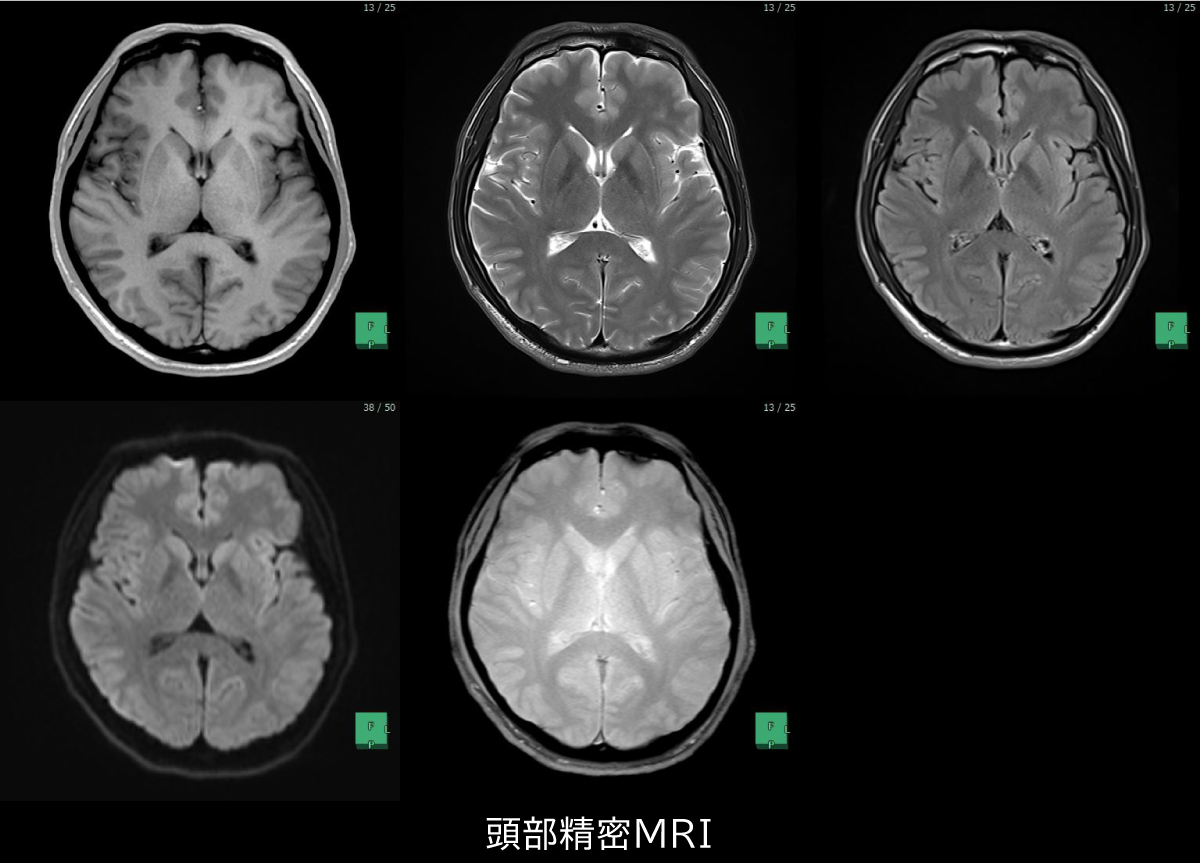

MRI・MRA検査は、X線を使用せず、強力な磁場を利用して頭部を撮影します。脳の断層写真を撮影し、脳腫瘍や脳梗塞を鮮明に写し出す「MRI」、脳の血管を立体的に写し出し、血管が狭くなっているところや脳卒中の前兆を発見する「MRA」という2種類の検査があります。MRAは、MRIとセットでお受けいただく必要があります。

受診者にやさしい検査機器

当センターのMRはトンネルが広いタイプを採用し、狭い所が苦手な方でも受診しやすい環境を整えております。